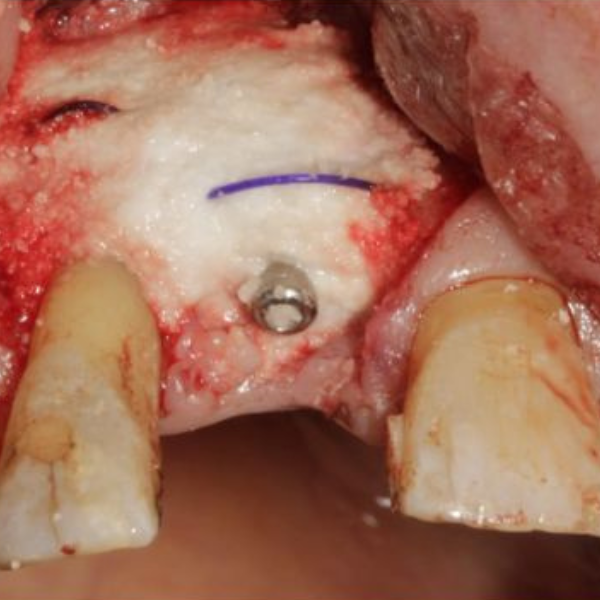

Resorbable Suture Tenting

Pain from a mobile upper right central incisor that had received trauma approximately ten years prior to presentation.